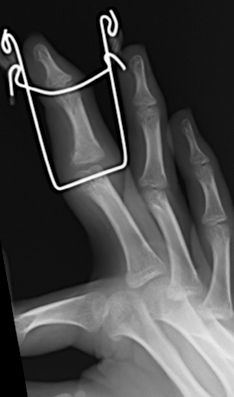

A menudo las radiografías convencionales, anteroposterior y lateral de codo, pueden infravalorar el desplazamiento real, por lo que se recomienda la realización de una proyección oblicua si fuera necesario, siendo ésta, la que mejor valora el desplazamiento. La línea de fractura va desde la superficie articular hasta la metáfisis distal del húmero. Las fracturas no desplazadas o mínimamente desplazadas (<2 mm) con integridad de la superficie articular se pueden tratar de forma conservadora mediante férula braquial y controles periódicos para valorar un posible desplazamiento secundario. Las fracturas desplazadas (>2 mm) precisan tratamiento quirúrgico. Si existe una afectación del cartílago articular, (evidenciado por RM o artrografía, está indicada la reducción abierta y estabilización con agujas de Kirschner (Figura 8). Una disección cuidadosa, respetando la zona posterior del cóndilo minimizará los riesgos de necrosis avascular del cóndilo humeral. Si la superficie articular está intacta, la reducción cerrada y estabilización con agujas de Kirschner es suficiente. La reducción anatómica de la superficie articular se realizará gracias a la visualización directa. En ocasiones, es difícil la reducción y la dorsiflexión de muñeca, relajando los músculos dorsiflexores, facilitará la reducción. La osteosíntesis se realizará con dos agujas de Kirschner lisas, con el punto de entrada posterior a la incisión y colocadas de forma paralela o divergente. A diferencia de las fracturas supracondíleas, en las que 3-4 semanas de inmovilización es suficiente, la inmovilización de las fracturas del cóndilo deben mantenerse por lo menos durante 4 semanas para evitar el riesgo de pseudoartrosis. Las agujas de Kirschner no se deben retirar hasta comprobar signos radiológicos de consolidación. Es importante informar a los padres de la posibilidad de aparición de una prominencia lateral, a menudo confundida con un cúbito varo, provocada por el hipercrecimiento óseo asociado a la atrofia de la musculatura. La rigidez articular es más frecuente que en las fracturas supracondíleas. La utilización de férulas dinámicas disminuye el riesgo de esta complicación.

Figura 8: a-d, Imagen radiografica de fractura del cóndilo lateral con desplazamiento articular. Tratamiento quirúrgico mediante reducción abierta y osteosíntesis.